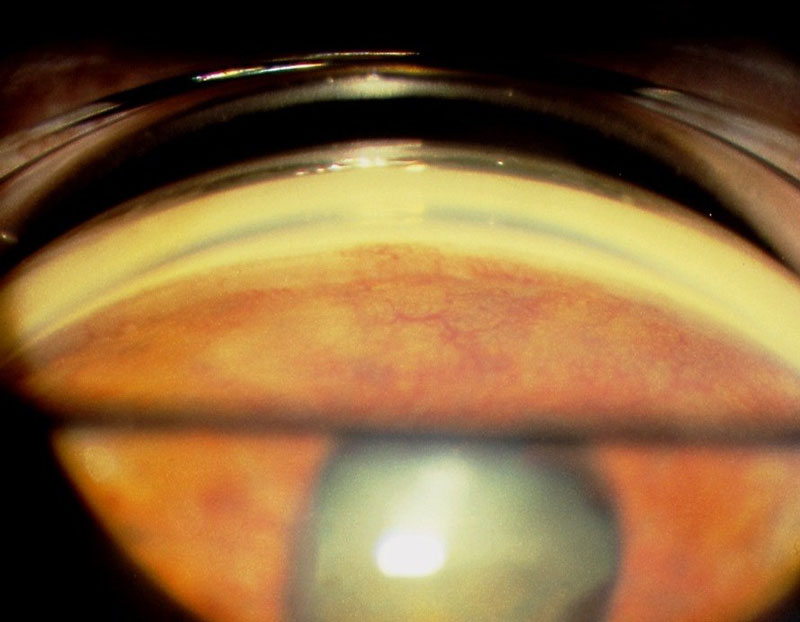

홍채(iris)에 발생하는 신생혈관을 홍채신생혈관, NeoVascularization at iris , NVI 라고 하며,

전방각(angle)에 발생하는 신생혈관을 전방각신생혈관, NeoVascularization at Angle, NVA 라고 합니다.

NVI와 NVA는 모두 비정상적인 혈관이기 때문에,

혈관에서부터의 누출이 심하고, 방수내의 비정상적인 염증세포등의 존재로 인해, 안압이 상승하게됩니다.